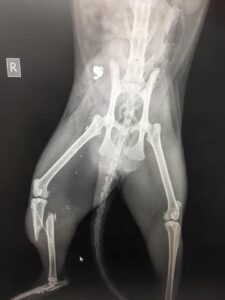

Missy, a 3-year-old Maine Coon from Upper Plain Rd, was shot twice this week — shattering her front leg into 22 pieces and breaking the tibia and fibula in her back leg.

Infections have already set in and Vetcare veterinary director Heidi Ward-McGrath said: “We’ll be lucky if we can save her front leg”.

“It’s got several things that make it surgically difficult — it’s infected, and it’s in lots of pieces.”

“I’ve gone and taken out lots of pieces of shrapnel – about 11 pieces in the front leg.”